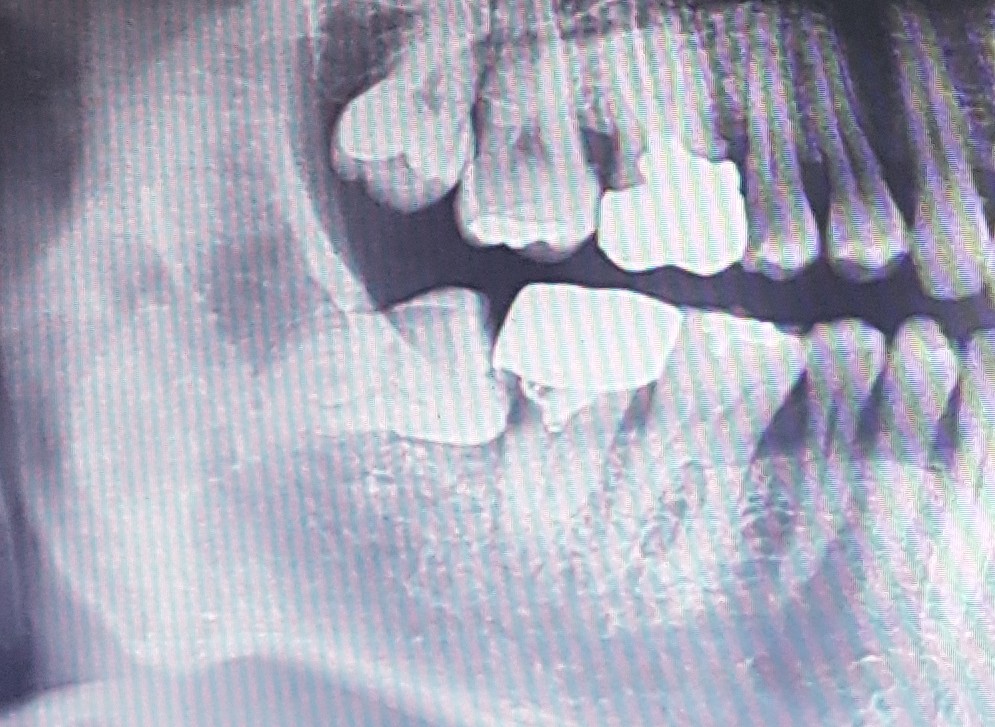

| Subject | 매복사랑니 꼭 발치해야하나요 |

치과 검진을 가서 엑스레이를 찍었는데 매복사랑니가 아래 양쪽에 있더군요. 완전 누워있어서 있는지도 몰랐어요. 그런에 선생님이 매복사랑니는 발치하는게 좋고 뽑으려면 대학병원가서 뽑으라 하시더군요. 인사드리고 나와서 검색 좀 해보는데, 애낳는 것보다 매복사랑니 뽑는게 훨씬 아팠다 등등의 후기를 보니 몸이 덜덜 떨리네요... 0